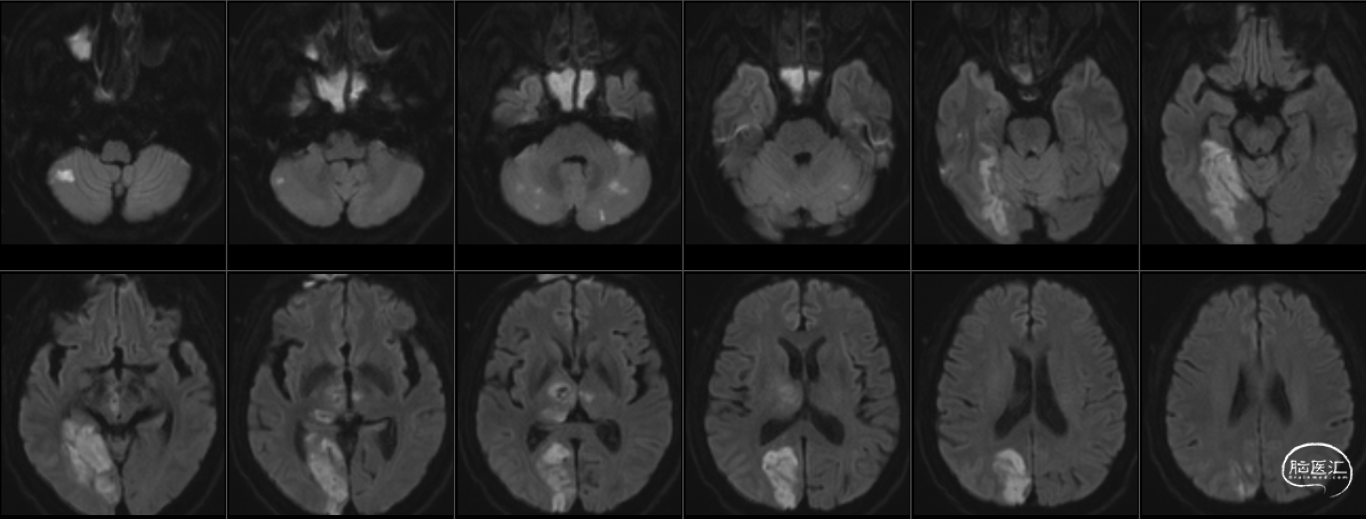

术后6天复查MR